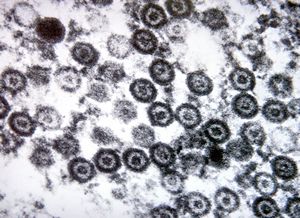

M,10y. | herpetic encephalitis